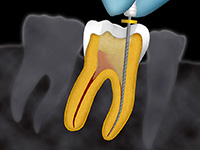

traitements endodontiques

Une carie profonde exige souvent un traitement endodontique avant la restauration de la dent, car les bactéries et leurs toxines se sont développées dans les racines.